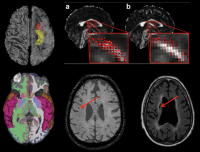

A sample of brain imaging studies from the laboratory of Adam Brickman at Columbia University Vagelos College of Physicians and Surgeons.